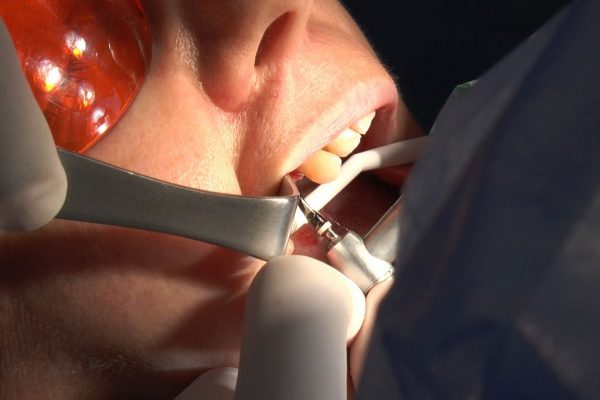

W ostatni weekend czerwca 2018 roku kursanci II Sezonu Preludium Implantologii odbyli piątą, finałową sesję, która w całości podporządkowana była praktyce. W ciągu dwóch dni zabiegowych Lekarze uczestniczący w szkoleniu przeprowadzili szereg zabiegów pod kierunkiem dr n.med. Violetty Szycik. Wszczepili 17 implantów oraz przeprowadzili ekstrakcje i zabiegi regeneracyjne kości. Zabiegi były wykonywane także w sedacji dożylnej z udziałem specjalisty anestezjologii i intensywnej terapii dr Jolanty Grzybowskiej. Preludium implantologii to nowy program edukacyjny dla adeptów implantologii stomatologicznej, którego celem jest wprowadzenie do implantologii poprzez pozyskanie wiedzy w szerokim zakresie i uwzględnieniem szczegółów mających decydujące znaczenie dla powodzenia leczenia implantologicznego. Ale tak jak wszystkie szkolenia w Instytucie Vivadental, w tym wiodące Practiculum Implantologii, zorientowane jest na praktyce i samodzielnym wykonywaniu zabiegów pod kierunkiem Mentora. To najlepsza edukacja w medycynie zabiegowej, a zarazem najlepszy start do implantologii.